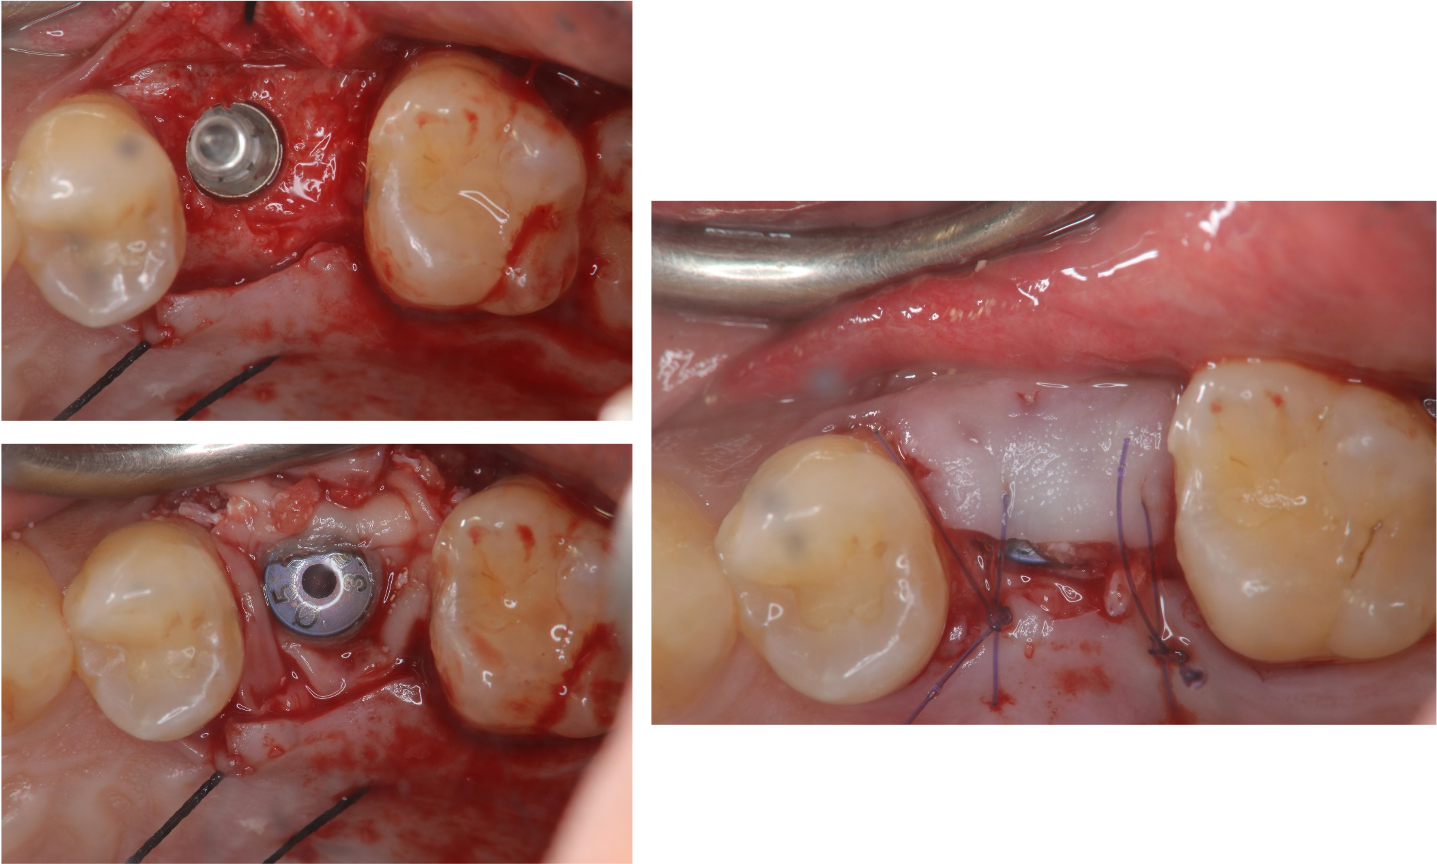

電腦定位手術導板

植牙與PRF加速癒合